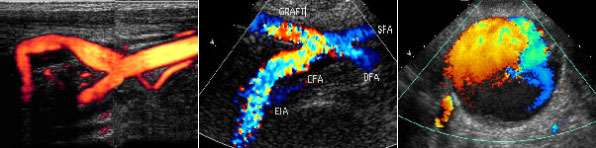

À°¾ÈÀ¸·Î º¸ÀÌÁö ¾ÊÀ» Á¤µµ·Î ±íÀº Á¤¸Æ·ù¿¡ ´ëÇÏ¿©´Â ÃÊÀ½ÆÄÀ¯µµÇÏ¿¡ Ç÷°ü °æÈ­¿ä¹ýÀ¸·Î ½Ã¼úÇÕ´Ï´Ù. ÃÊÀ½ÆÄ¸¦ ÀÌ¿ëÇÏ¿© Ç÷°ü°æÈ­Á¦¸¦ ÁÖÀÔÇÒ ºÎÀ§¸¦ Á¤È®ÇÏ°Ô Ã£Àº ´ÙÀ½ ÃÊÀ½ÆÄ È­¸éÀ» º¸¸é¼­ ¾à¹°À» ÁÖÀÔÇÏ´Â ¹æ¹ýÀÔ´Ï´Ù.